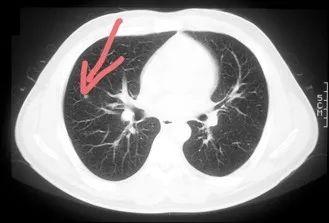

1、肺癌筛查:超低剂量 CT

2015 年,癌研有明医院体检中心引进了超低剂量 CT,辐射剂量从 1.54 mSv 降为 0.40 mSv;2016 年经过调整拍摄条件,进一步将剂量降低到 0.12 mSv,达到与 X 光片同样程度,但效果却远远优于 X 光片,可发现毫米级的肺部肿瘤。

5 mm 大的微小肺癌